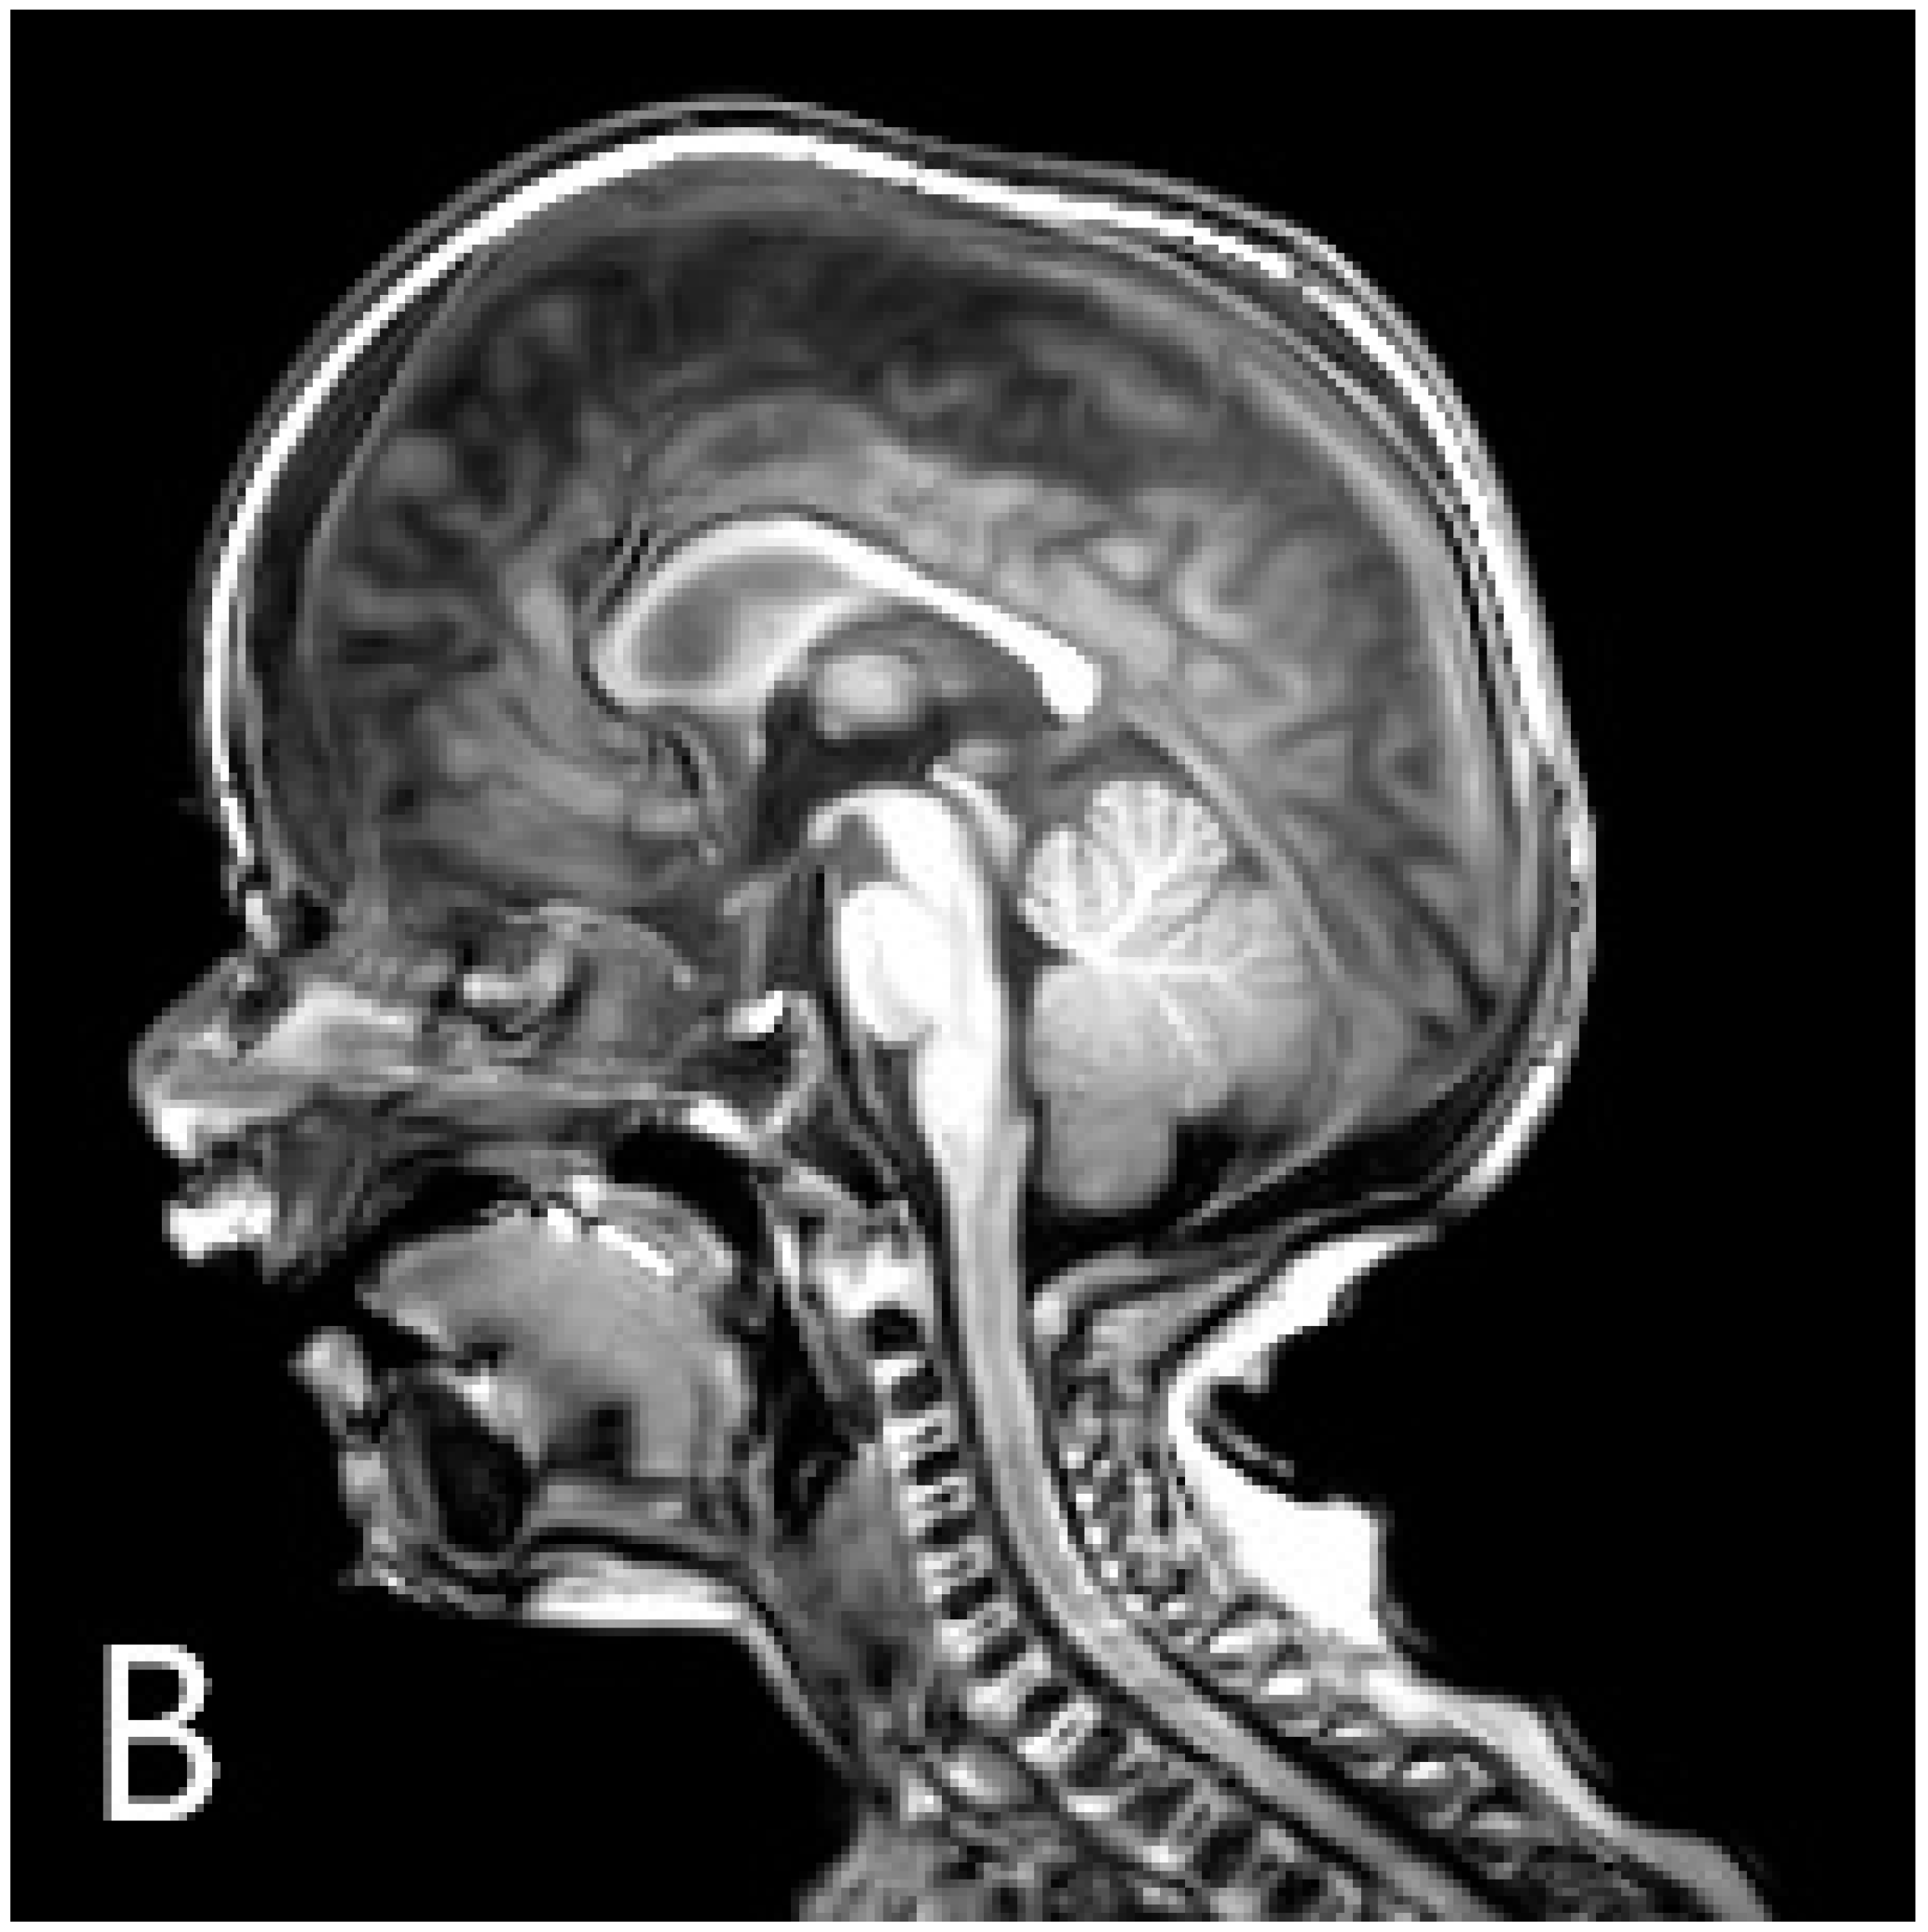

Resolution of osteopetrosis could be seen on MR imaging that took place 6 months after the transplantation, and radiography also demonstrated the recovery of the disease phenotype (Figure 2A).

Figure 2.

Chest radiography (A) shows the disappearance of skeletal malformations 6 months after the transplantation. At this time, sagittal T1-weighted MR image (B) described the unusual morphology of the calvaria: craniosynostosis.

However, radiological normalisation was not apparent in one region, the calvaria: neurocranial sutures progressed to ossify even though osteoclast resorptive function had been initiated in other parts of the skull and the skeletal system (Figure 2B). Neurosurgery was confronted with the necessity of craniotomy considering the danger of increased intracranial pressure secondary to craniosynostosis. The reconstructive operation was successfully performed. In the 15th month, at the time of the writing of the manuscript, the patient remained on an adequate course of neuromotor development, had stable haematopoiesis, and achieved recovery of the disease phenotype related to bone metabolism.